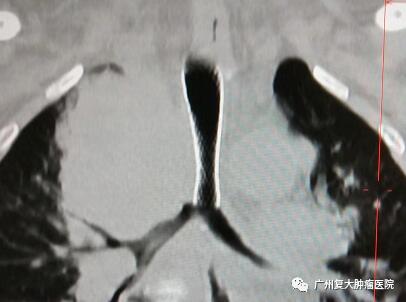

同样,食管癌手术、放疗后复发等多种因素导致吻合口狭窄是常见的问题,患者不能进食,生活质量下降。患者张先生也因喉咙不适,吞咽困难,在当地医院进行检查后被确诊为“食管癌”,并接受了食管癌根治术,术后出现吻合口瘘及吻合口狭窄,实行3次食管扩张术。为抑制肿瘤的增长,他开始进行放化疗治疗和药物治疗,但不仅化疗都让张先生痛苦万分,还出现吞咽困难,胸闷心慌,呼吸困难,左上肢肌力减退、疼痛、麻木等症状。

为进一步诊疗,张先生来到我院就诊。张先生因严重气管狭窄引起呼吸困难,时间急迫,在与家属多次沟通并取得同意后,在DSA+CT影像技术引导下,牛立志院长为其实行紧急气管支架植入+肿瘤射频消融术。术后第二天,张先生下床活动自如,原来胸闷、心慌、呼吸困难等症状全都消失了。他激动地找到牛院长说:“牛院长,太感谢你啦,我现在感觉呼吸顺畅很多了。”

牛立志院长表示,对于食管癌或其他病因引起气道狭窄的患者,气管支架植入治疗目的就是可使不通的管道变得通畅,迅速缓解腔道狭窄的症状,改善患者呼吸状态,避免窒息发生,提高患者生活质量并为后续治疗奠定了基础。